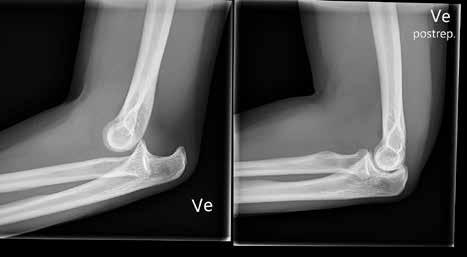

Det betyr, ifølge Famorca, at man kan vinke farvel til ukomfortabel liggestilling, eller til for eksempel å måtte strekke ut en vond arm i forbindelse med MR.

Han forteller at han selv blant annet kunne ligge på rygg og fikk en langt mindre ubehagelig opplevelse enn han før ville fått, da han nylig var til MR på grunn av en tennisalbue.